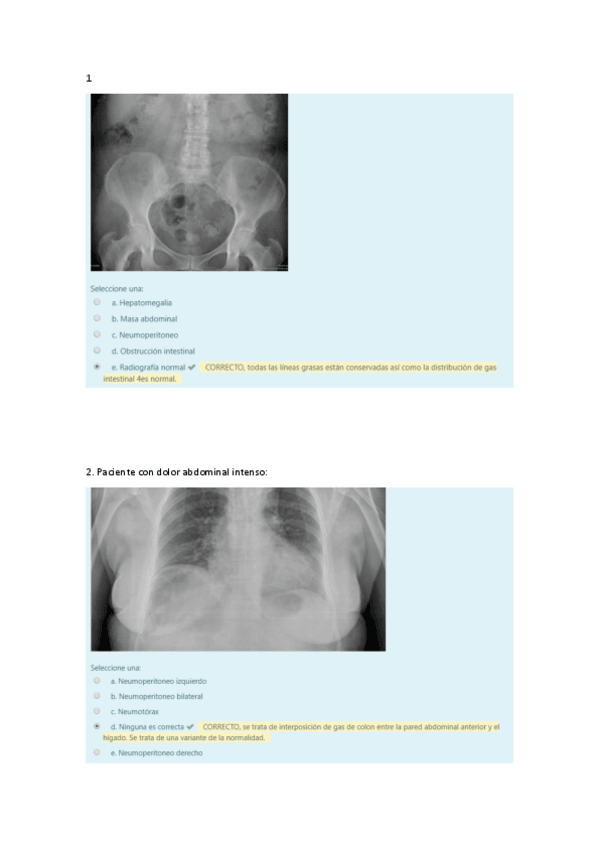

están recogidas todas las preguntas con las imágenes y respuestas correctas